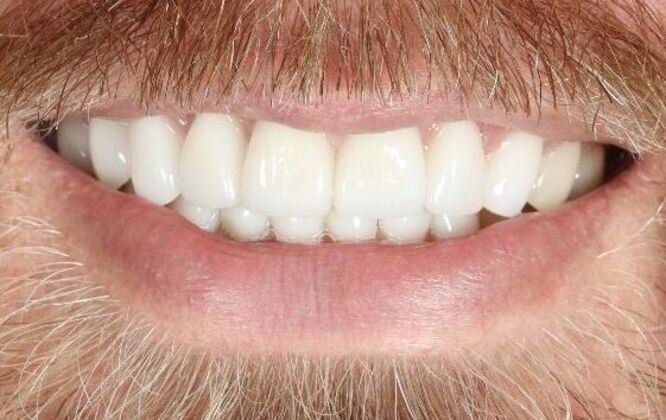

Porcelain Veneers: Craig

Description

Patient presented to office with worn teeth and decay from silent acid reflux. The best treatment option for him was to cover his teeth with porcelain restorations to restore the lost enamel and protect the remaining tooth structure.